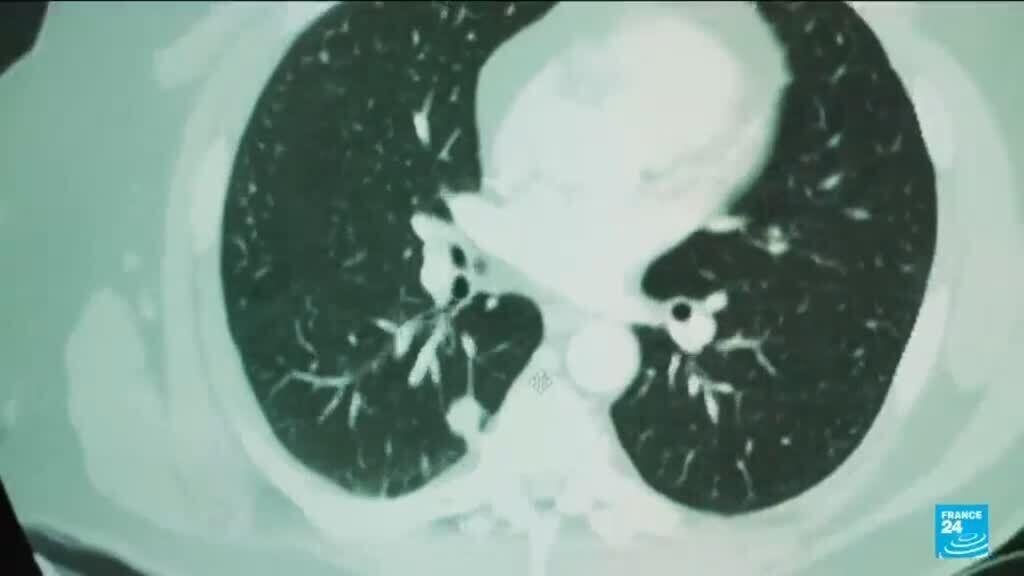

In an exciting development, researchers have demonstrated that AI can significantly improve the identification of breast cancer, ensuring that more cases are detected during routine check-ups. This technology addresses the challenges radiologists face, particularly with increasing workloads and the necessity for accurate interpretations of mammograms.

The goal of employing AI in this context is clear: to enhance the capabilities of healthcare providers. Rather than supplanting human expertise, AI serves as a vital tool that assists radiologists in managing their tasks more efficiently. The findings from the Swedish trial illustrate that, with AI’s intervention, clinicians can focus on patient care while benefiting from improved diagnostic accuracy.